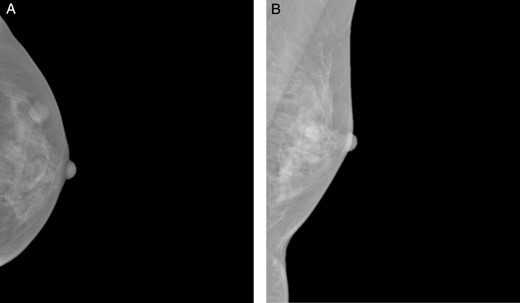

A 37-year-old Chinese female presented with a lump in the left breast that was slowly growing over a duration of 8 years. Aside from a history of amenoblastoma of the jaw which was excised 3 years ago, she has no significant medical history. On physical examination a firm 1-cm nodule was palpable at the 3 o'clock position of the left breast. Mammography showed a well-circumscribed opacity in the left breast (Fig. 1) and ultrasound revealed an ovoid 1.5 × 1.5 × 0.9 cm heterogeneous solid hypoechoic nodule with well-defined, regular margins (Fig. 2). The lesion contained some anechoic areas suggestive of cystic clefts which are consistent with sonographic features of a phyllodes tumour [1, 2].

Sonographic views of an ovoid well-marginated nodule containing some cystic clefts. This lesion was initially thought to represent a phyllodes tumour.

On mammography, most schwannomas appear as well-circumscribed opacities. In certain cases, they may be mammographically occult or may present as ill-defined soft tissue densities [3]. Sonographically, they are generally described as well-defined hypoechoic lesions. Other features suggestive of a schwannoma on ultrasound include target sign (hyperechoic centre and hypoechoic periphery), posterior acoustic enhancement and peripheral nerve continuity. However, these features may also represent other peripheral nerve sheath tumours like neurofibromas [8]. The mass in our patient had cystic areas which were also reported by Lee [5] and Uchida [3].